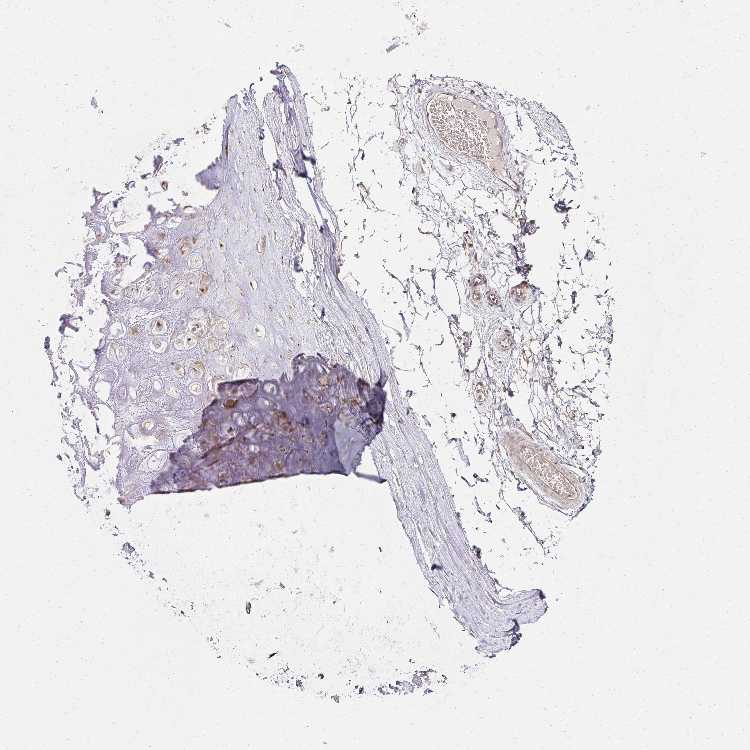

SOFT TISSUE 2 - Antibody stainingi

Antibody staining in the annotated cell types in the current human tissue is reported as not detected, low, medium, or high, based on conventional immunohistochemistry profiling in selected tissues. This score is based on the combination of the staining intensity and fraction of stained cells.

Each image is clickable and will lead to virtual microscopy that enables deeper exploration of all samples and also displays staining intensity scores, fraction scores and subcellular localization as well as patient and tissue information for each sample.

Antibody HPA046979Antibody HPA054254Antibody CAB025901

Fibroblasts LowNot detectedMedium

Peripheral nerve LowNot detectedNot detected